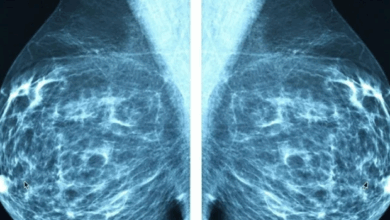

[highlight]Haarverf is eerder in verband gebracht met verschillende soorten kankers, waaronder tumoren in de borst, blaas, eierstokken en de hersenen en ook leukemie[/highlight]. Er zijn tevens zorgen dat steeds meer mensen allergischer worden voor de inhoud, soms met fatale gevolgen. De verkoop van de haarverfpakketten alleen al in de winkels heeft een geschatte waarde van 421 miljoen dollar per jaar, en dit cijfer zal naar verwachting alleen maar toenemen naarmate de bevolking vergrijst.